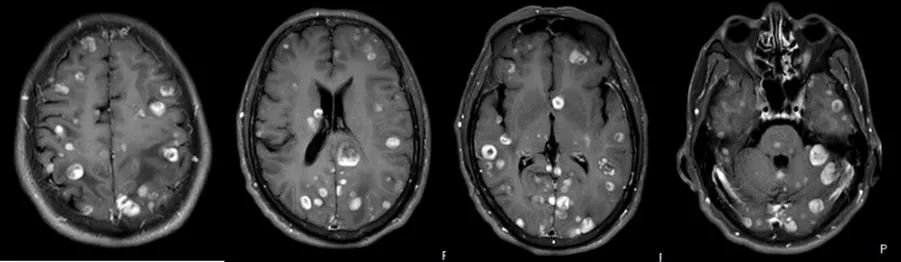

2024年9月,张先生因言语混乱、行走不稳来济宁市第一人民医院就诊,经全面检查确诊为右肺腺癌(IV期)伴多发脑转移,基因检测显示无敏感突变,影像学检查显示颅内如繁星般散布着多个转移灶,病情危急。肿瘤科陈卫东教授团队立即组织多学科会诊,制定个体化治疗方案。先行全脑放疗控制颅内病灶,同步给予脱水降颅压治疗,密切监测神经系统症状变化。放疗结束后,患者出现预期中的放射性脑水肿,一度陷入昏迷,医疗团队迅速调整方案,加强降颅内压治疗,同时给予营养支持、预防癫痫等治疗并加强卧床护理。

在医护人员的精心守护下,患者终于在昏迷3天后奇迹般苏醒,随后病情逐步稳定。目前,患者已完成后续6周期全身化疗,近期复查显示脑转移灶明显缩小,肺内病灶稳定,疾病得到有效控制。

图为:放疗前及近期颅脑MRI对比